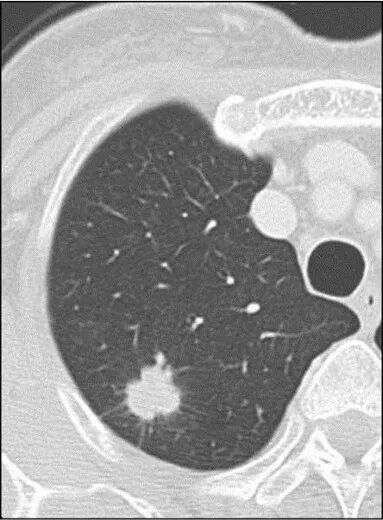

右下肺磨玻璃结节

2月后复查变淡消散